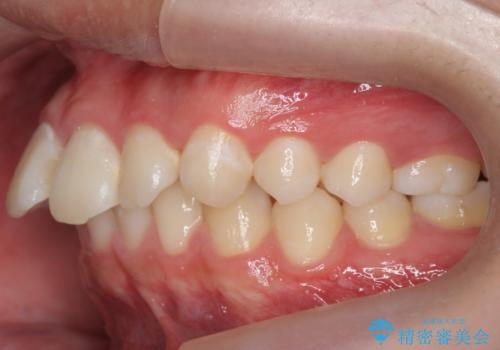

出っ歯が気になる 歯をぬかずに治療

- 前歯が出ているのを気にして来院。

左のかみ合わせが1本分ずれていましたが、機能的には問題ないのでそのまま変えずに治療しています。

ずれている分を、上の歯を1本抜くか(ワイヤー矯正になります)、右上の奥歯を1本分後ろに送るか、そのまま前歯を並べるのかを選んでいただきました。

右のかみ合わせをそのままに、最小限の動かし方で見た目を改善しました。